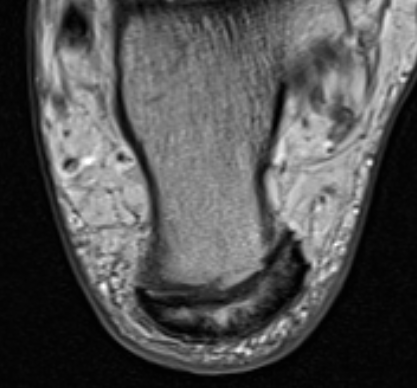

Retrocalcaneal bursitis with Haglund's

Partial tearing at insertion with retrocalcaneal bursa

Tendon thickening, Haglund's deformity and retrocalcaneal bursa